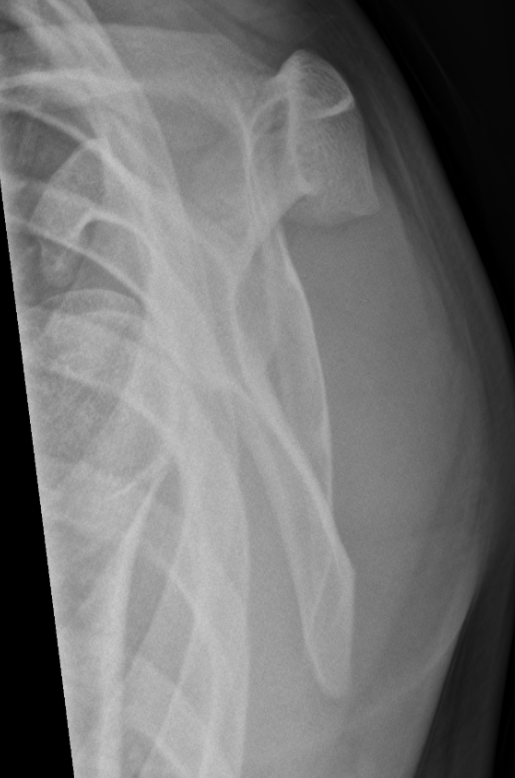

3. Anterior glenohumeral dislocation on scapular Y-View